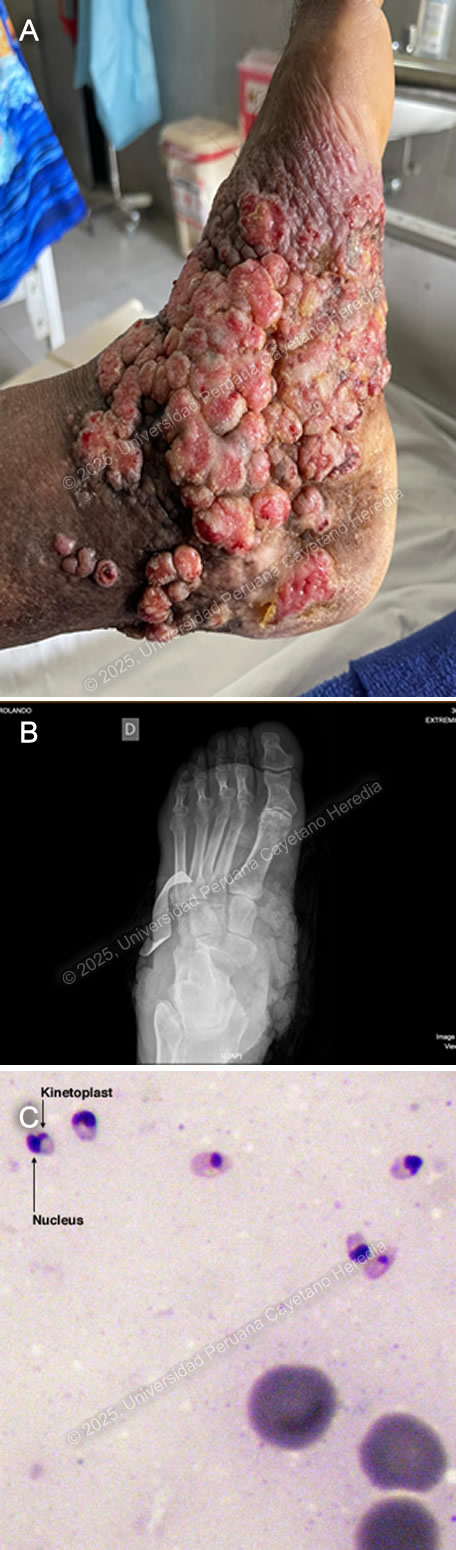

![]() History: A 70-year-old male patient with no significant past medical history presented to the outpatient clinic at HCH with a six-year history of expanding, painless skin lesions on his left foot. Six years before admission, he developed a painless, non-pruritic, 1 x 1.5 cm non-healing papule that became ulcerated on the dorsum of his left foot. At that time, he sought care at a local health center, where he received three intralesional pentavalent antimonial injections over three consecutive days, with partial clinical improvement. Five years before admission, the lesion increased in size to 5 x 5 cm and was accompanied by localized swelling. The lesion continued to expand, and four months before admission, it became moderately painful, impairing his daily activities. Due to persistent symptoms, he attended the dermatology clinic and was admitted for further workup and management. Epidemiology: The patient was born and resides in La Merced, a city located in the high jungle of Peru, where he works in agriculture cultivating coffee and fruits. He frequently walks barefoot in the jungle soil and experiences numerous mosquito bites. He denies any travel outside his place of birth. He has no known tuberculosis (TB) contacts but reports that multiple neighbors throughout his lifetime have presented with similar non-healing cutaneous ulcers. Physical Examination on admission: BP: 110/80 mmHg, HR: 70 bpm, RR: 20 breaths per minute, T: 36.5°C, SpO2: 98% on room air. The skin examination revealed multiple tumor-like, verrucous, confluent hyperkeratotic plaques with irregular and poorly defined borders in the middle and lateral malleolar regions and on the heel of the left foot, with hyperpigmentation and scaling (Image A). The rest of the examination was normal. Laboratory: Hemoglobin: 9.4 g/dL (MCV 92 fL, MCHC 33 g/dL), Hematocrit: 29%, WBC: 4,400/µL (0% bands, 65.1% neutrophils, 8.7% eosinophils, 0.5% basophils, 11.3% monocytes, 14.4% lymphocytes), Platelets: 433,000/µL, Creatinine: 0.81 mg/dL, Sodium: 140 mEq/L, Potassium: 4.9 mEq/L, Chloride: 104 mEq/L. Serology for HIV, HTLV-1, RPR, and Hepatitis B and C were all negative. A foot X-ray showed no bone involvement (Image B). A Giemsa-stained scraping from the border of a lesion was performed (Image C; reference image, original of low quality). UPCH Case Editors: Carlos Seas, Course Director / Mario Suito, Associate Coordinator |

![]() ![]() Discussion: GeneXpert ultra and acid-fast bacilli (AFB) staining from the tissue biopsy were negative, as was the TB liquid media (MGIT) culture. KOH and fungal cultures were also negative. The Montenegro intradermal hypersensitivity test was positive (30 x 35 mm). A skin punch biopsy revealed parakeratosis and acanthosis associated with a lymphohistiocytic inflammatory infiltrate and epithelioid granulomas; however, no definitive amastigotes were seen. A kinetoplast DNA PCR (kDNA PCR) for Leishmania sp. was positive, confirming the diagnosis (Image D). Finally, the patient presented a remarkably positive therapeutic response after treatment with Amphotericin B, showing marked improvement of the lesion (Image E). Leishmaniasis is endemic in 88 countries, including Brazil, French Guiana, Colombia, Ecuador, Bolivia, and Peru (1). The most common manifestation is cutaneous leishmaniasis (CL), which affects 10 million people worldwide. Affected patients typically live in or have a history of travel to endemic areas. In Peru, over 7,000 cases are reported annually (2,3). CL in Peru is a zoonosis caused by Leishmania species, almost exclusively from the subgenus Viannia, particularly L. peruviana, L. braziliensis, L. guyanensis, and L. panamensis. Humans become infected when the sandfly vector (Lutzomyia sp.) inoculates promastigotes into the host’s bloodstream while taking a blood meal. These promastigotes are phagocytized by macrophages, where they develop into amastigotes that multiply until they are released and infect other cells. CL usually develops 2-8 weeks after inoculation. The most common presentations include the localized-ulcerative form, the nodular or sporotrichoid form, and the diffuse and disseminated cutaneous forms. Less common manifestations include plaque, psoriasiform, and verrucous leishmaniasis, which represent 2-5% of all CL cases (4). Verrucous leishmaniasis is a rare subtype of the already infrequent atypical cutaneous leishmaniasis subgroup. It is classically described as hyperkeratotic plaques covered by thick, adherent crusts. Diagnosis relies on identifying high-risk patients based on compatible clinical manifestations and the appropriate epidemiological exposure, followed by specific parasitological diagnostic tests. Most confirmatory tests require invasive tissue biopsies, where 1) direct microscopy with commonly used Giemsa stain reveals amastigotes, 2) culture from the lesion demonstrates promastigotes, and/or 3) PCR amplification detects genomic DNA from Leishmania sp. Serology has no role in the diagnosis of leishmaniasis. A positive Montenegro skin test demonstrates a delayed-type hypersensitivity reaction to Leishmania antigens but cannot differentiate between previous exposure and active disease. Speciation impacts treatment decisions regarding initiation, regimen selection, duration, and dosage. It can be performed using isoenzyme analysis requiring cultured promastigotes or molecular methods like PCR from a tissue sample (5). New World cutaneous leishmaniasis may be treated topically with paromomycin and gentamycin, intralesional injections of pentavalent antimonials, or physical methods such as thermal and cryotherapy (6). For patients with extensive (>5 cm) or multiple (≥ 5) lesions, immunosuppression, or species associated with mucosal disease (L. braziliensis, L. guyanensis), systemic treatment is recommended. Systemic options include intravenous pentavalent antimonials (SbV) (sodium stibogluconate, meglumine antimoniate) and Amphotericin B, as well as oral Miltefosine (7). Although no controlled randomized trials have demonstrated a significant statistical difference between amphotericin B and SbV, extensive cutaneous disease, such as in this case, is typically treated with Amphotericin B (8). References |